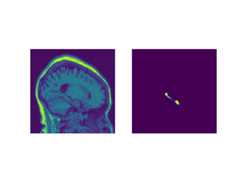

Input Image Visulization for checking

a) Original Image

b) CenterCrop Image

Dice Score for hippocampus segmentationADNI-LONI Dataset